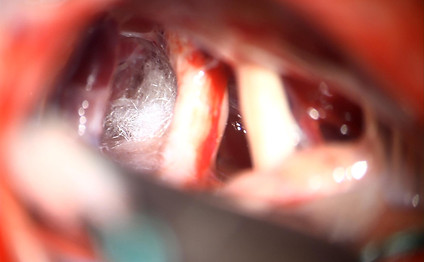

Sinoviāla cista

Redzama L4-5 līmeņa sinoviāla cista

Pēc operācijas sinoviālā cista vairs nav redzama